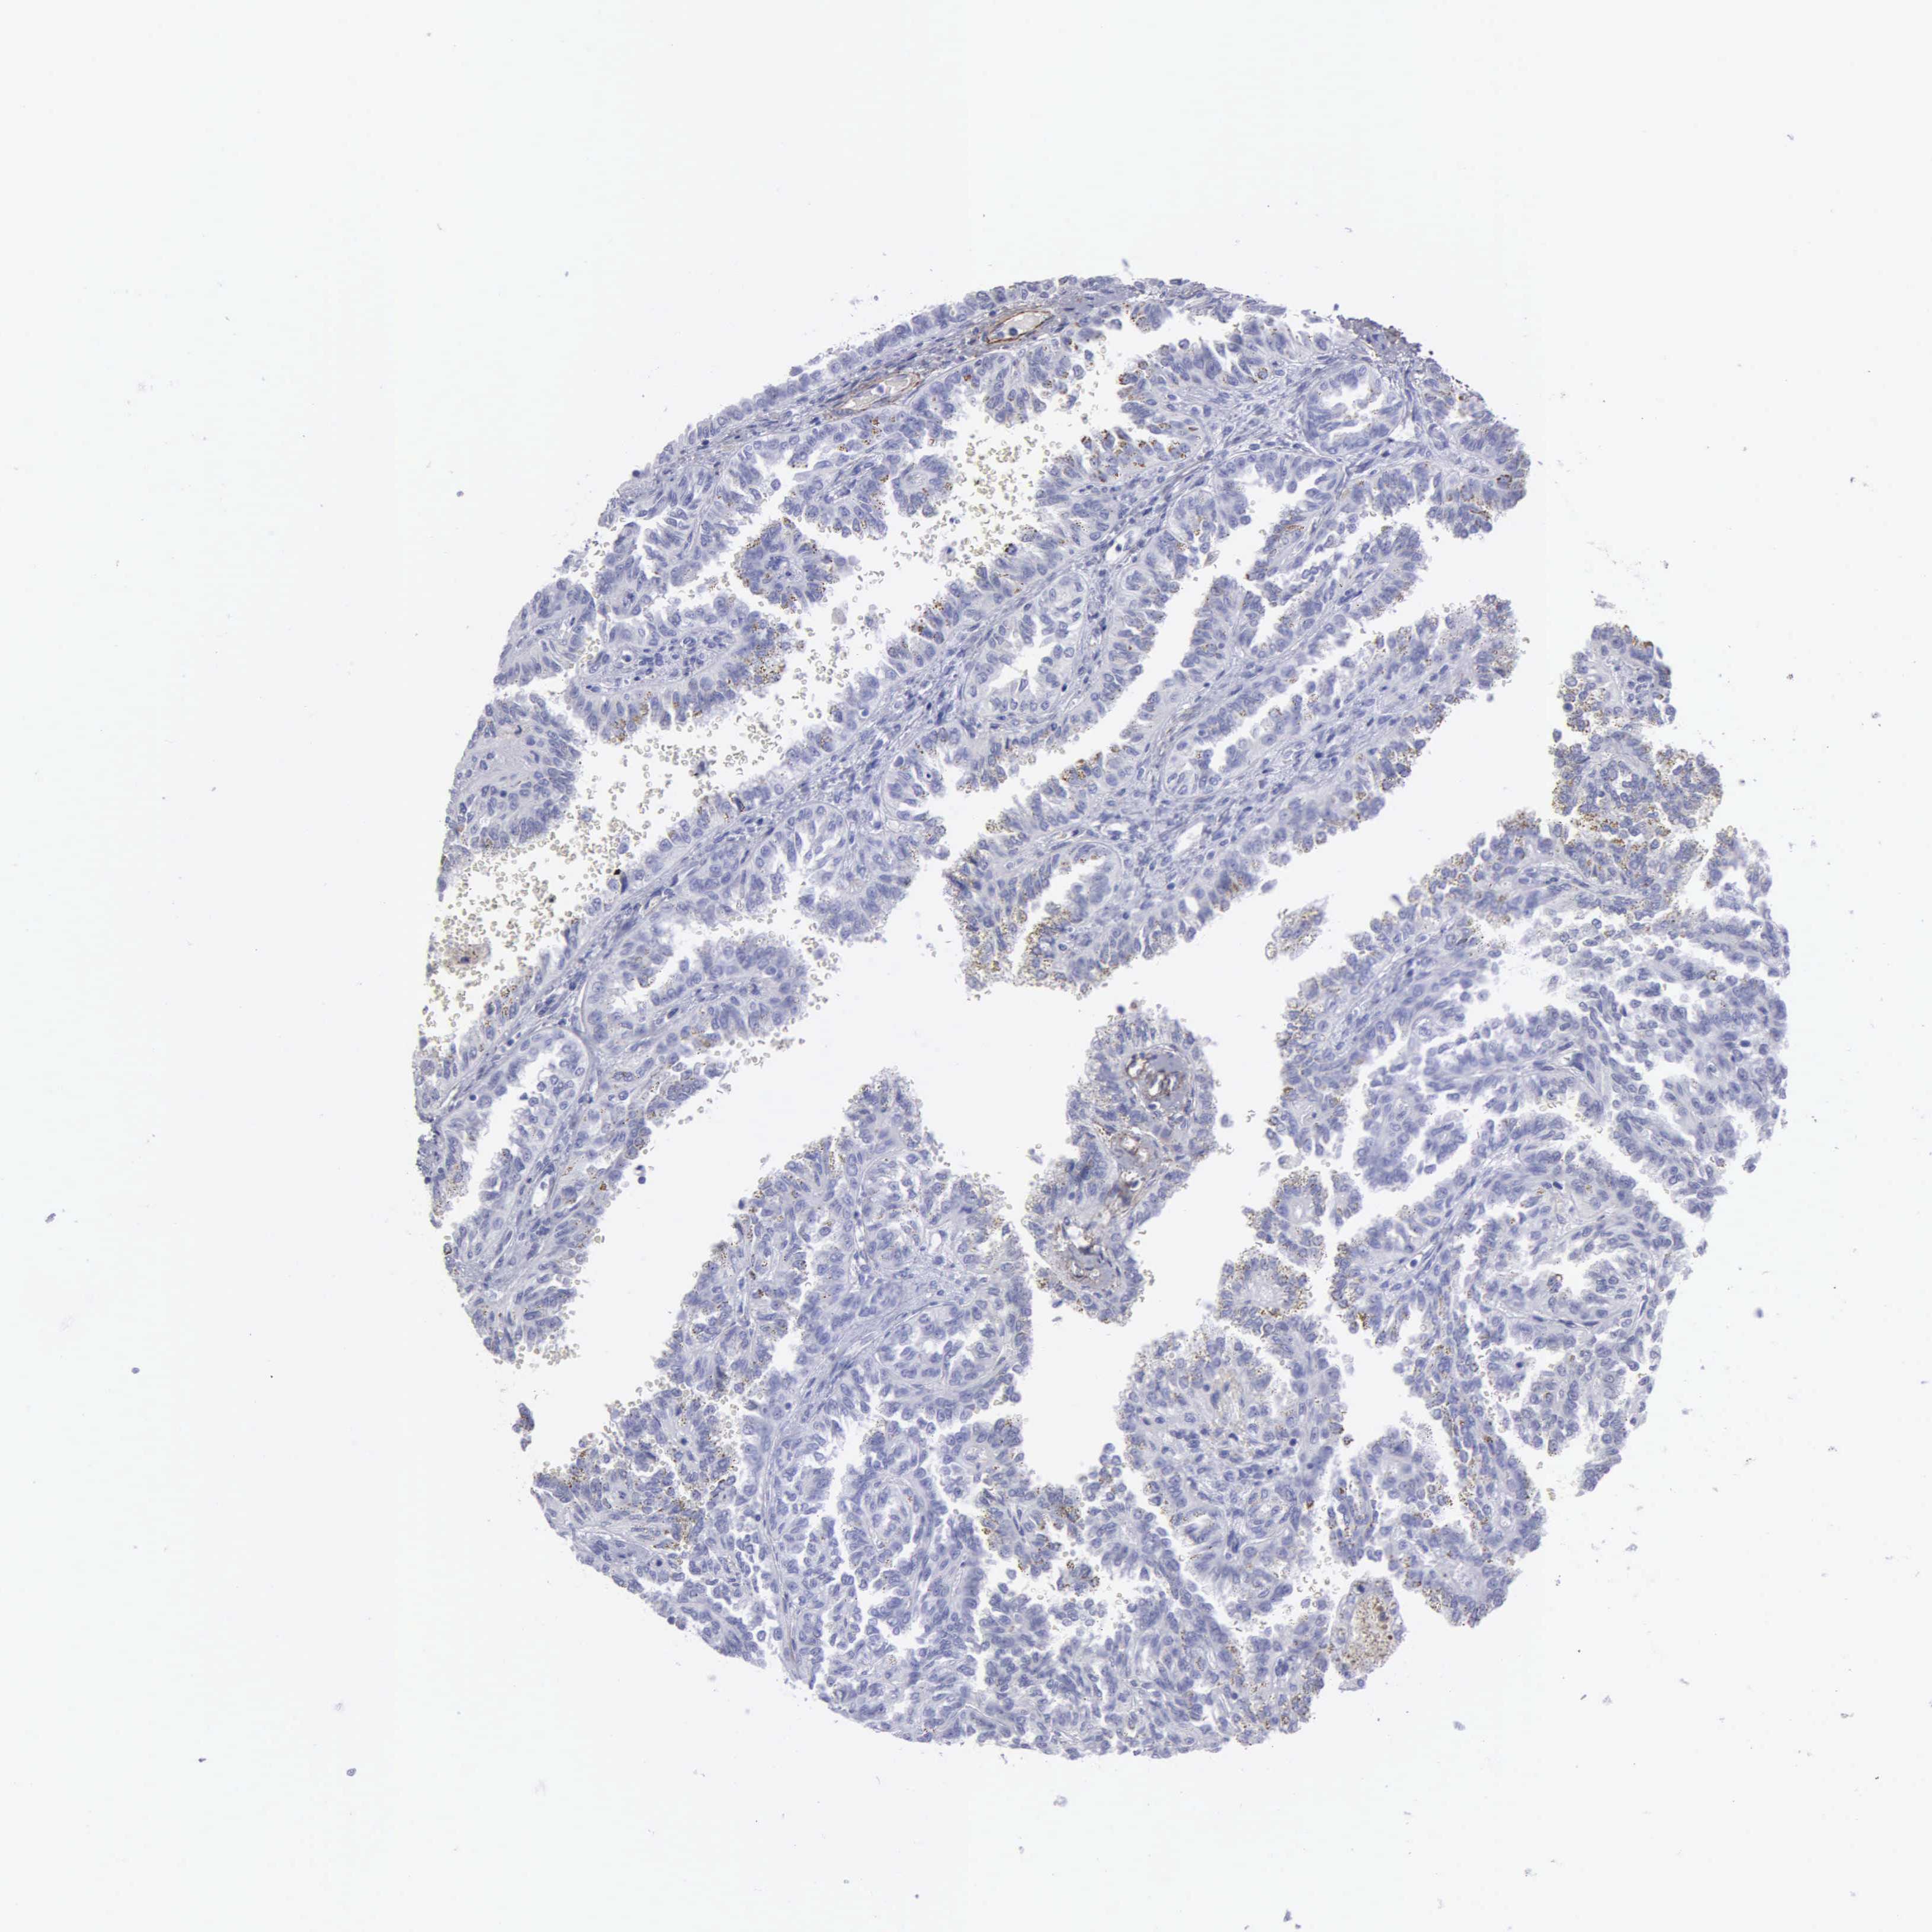

FBLN5